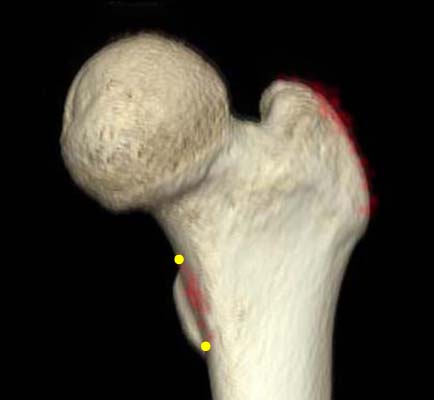

*Vertical distance from greater trochanter to fracture line. †Vertical distance from proximal boundary of lesser trochanter to fracture line. ‡The angle between the fracture line of the distal fragment and anatomical axis of the femur.